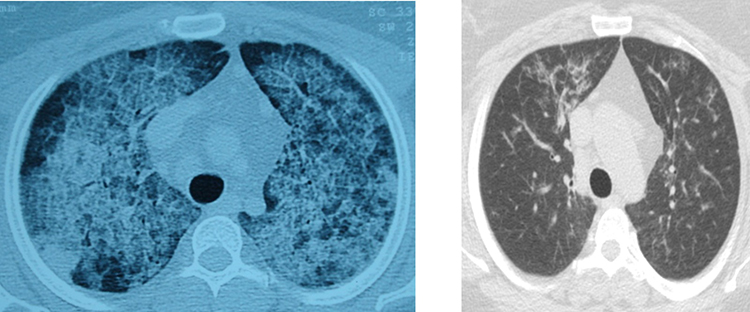

Hastalığın, kişinin kendi yağ ve proteinlerinin temizlenmesiyle görevli hücrelerdeki sorun nedeniyle akciğerlerdeki hava keseciklerinin birikmesi sonucu ortaya çıktığını aktaran Ergur, belirtilerin nefes darlığı, yorgunluk ve aşırı halsizlik olduğunu kaydetti. Ergur, hastalığın çoğu zaman astımla karıştırıldığını, tanının ancak ileri tetkiklerle konulabildiğini ifade etti.

Sadece deneyimli merkezlerde uygulanabilen akciğer yıkamasının, ameliyathane koşullarında, hastanın uyutularak her seansta 15-20 litre steril su verilmesi ve geri alınması yöntemiyle yapıldığını anlatan Ergur, şunları kaydetti:

"Bazı hastalar kendiliğinden düzelirken bazen yalnızca tek ya da birkaç yıkama yetebilmekte, nadiren sürekli birikim olması nedeniyle akciğer yıkamalarının tekrarlanması gerekebilmektedir. Bu durumda hastaların yeniden nefeslerine kavuşabilmeleri, deneyimli ekibin bu tedaviyi uygulaması sayesinde olabilmektedir. Yıkama esnasında başta koyu olan, beklediğinde şişenin dibinde çökelti oluşan yıkama sıvısının rengi giderek açılmakta ve bu durumda yıkama işlemi sonlandırılmaktadır."